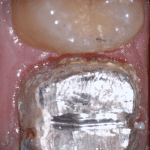

In this clinical video we demonstrate how to scan a molar preparation for the replacement of a crown with recurrent decay and open margins. The molar was root canal treated and the tissue was inflamed. the preparation was imaged and a temporary was fabricated to allow the tissue to heal properly.

The main point of this video is to show how to capture the contacts of the adjacent teeth and the deep marings